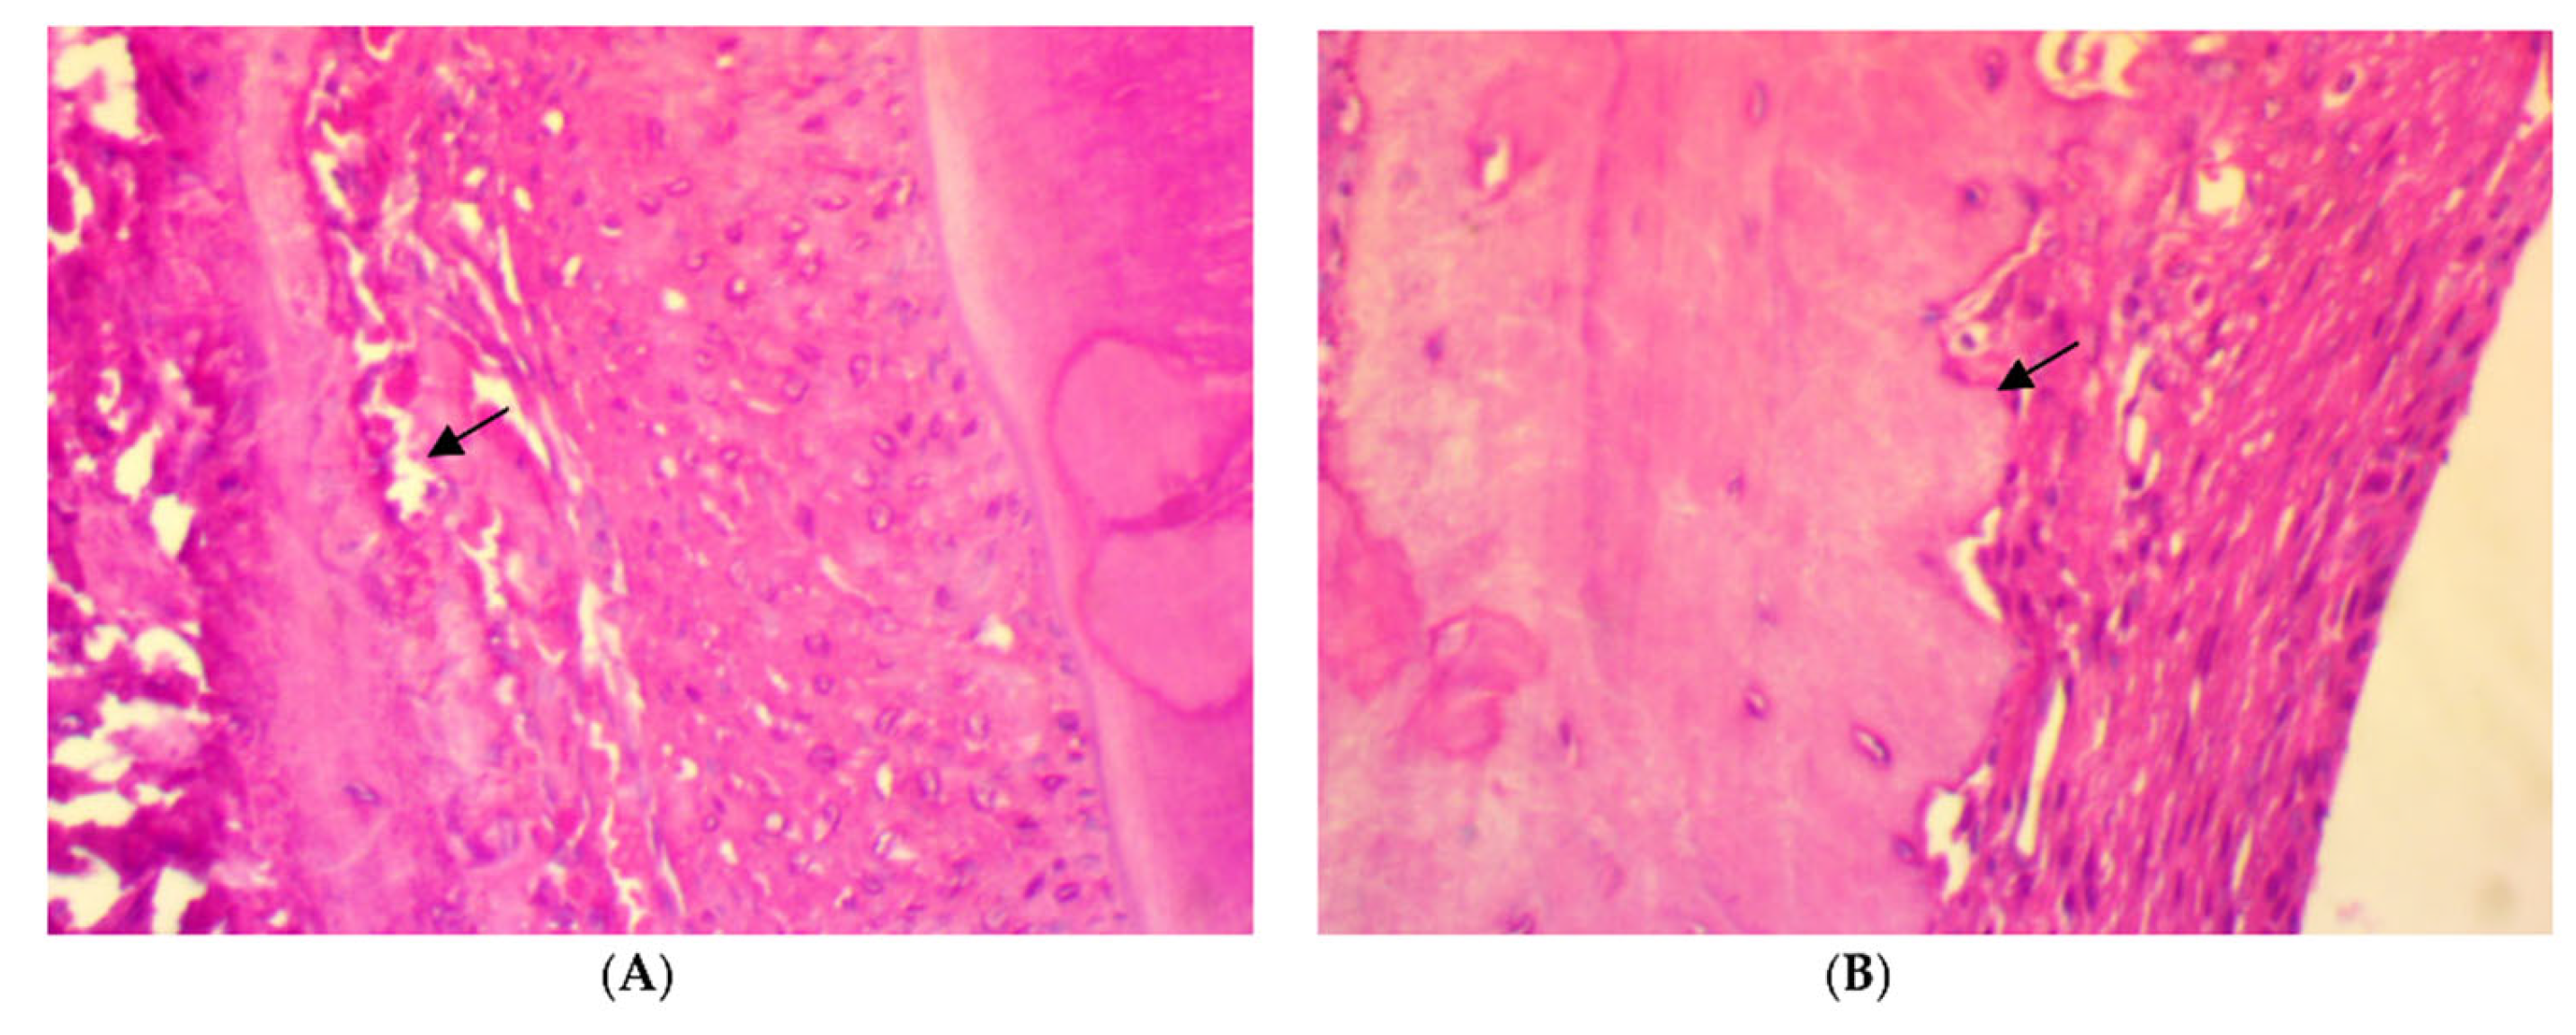

On the other hand, a significant deposition of iron in the bone trabeculae was noticed in the SRP+CU group only (Figure 6C,D). The iron deposits appeared as blue linear bands in the bone matrix at the surface of the bone trabeculae. In contrast, no detectable iron with the Perls’ staining was found in the SRP group and SRP+T groups (Figure 6A,B).

Figure 6.

Histopathological features of rat periodontal tissue in SRP group (A) and SRP group+T (B) after four weeks of treatment show bone trabeculae is unstained and the lamellar organization of the matrix is evident. The surface of the bone trabeculae is labeled in blue, indicating a deposition of iron (arrow) in SRP+CU treatment (C,D) (Perls’ stain ×400).